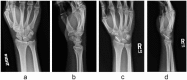

Background: Percutaneous techniques have been described for the treatment of nondisplaced scaphoid fractures, although less information has been reported about outcomes for unstable, displaced fractures. The aim of this study was to evaluate the union and complication rates following manual closed reduction and percutaneous screw placement for a consecutive series of unstable, displaced scaphoid fractures.

Methods: A total of 28 patients (average age, 27 years; 22 male/6 female) were treated for isolated unstable displaced scaphoid waist fractures. Closed reduction and percutaneous headless, compression screw fixation was successfully performed in 14 patients (average age, 32 years; 10 male/4 female), and the remaining 14 patients required open reduction. Patients who underwent percutaneous treatment were followed for radiographic fracture union and clinical outcomes.

Results: Thirteen of 14 fractures (93%) had clinical and radiographic evidence of bone union at an average of 2.8 months postoperatively. Average visual analog pain score at the time of union was 0.9. The average Quick Disability of the Arm, Shoulder, and Hand score at 2.5 years follow-up (range, 1.5-8.3 years) was 9.6 (range, 0.0-27.3). Complications included 1 case of nonunion and 1 case of intraoperative Kirschner wire breakage.

Conclusions: Manual closed reduction followed by percutaneous headless, compression screw fixation was possible in 50% of patients who presented with acute unstable, displaced scaphoid fractures. This technique appears to be a safe and effective method when a manual reduction is possible, and it may offer a less invasive option when compared with a standard open technique.